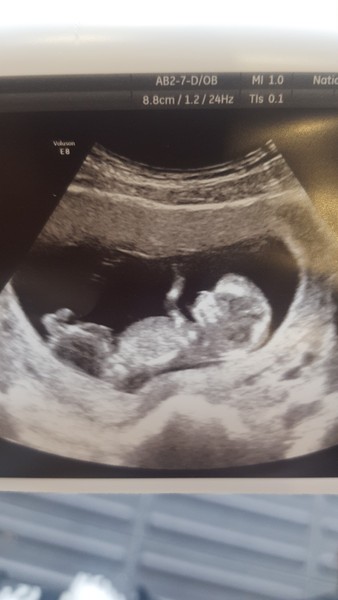

Saw my obstetrician today who gave me a stick scan, can't get enough of seeing this little one jumping about! So reassuring with everthing else going on ❤

@Chocolate89 amazing scan pic! how far along are you?

What a fab picture! Xx

@Chocolate89 that really is a beautiful clear scan pic 😍

Thanks ladies! 😊😊 I'm 11+4 but she reckons I might be a bit further as uterus is about an inch above the pelvis. I have a detailed scan in 2 weeks time so will get accurate measurements then!

What a lovely scan pic @Chocolate89 😀

Lovely clear scan picture Chocolate. The legs look really long compared to what I saw on my scan. It's amazing how fast they grow!

@Chocolate89 what a great scan picture! Bet you're pleased 😃

@Chocolate89 that scan is amazing!! 11 days until my scan not that I'm counting!

@Chocolate89 what a beautiful picture so clear!